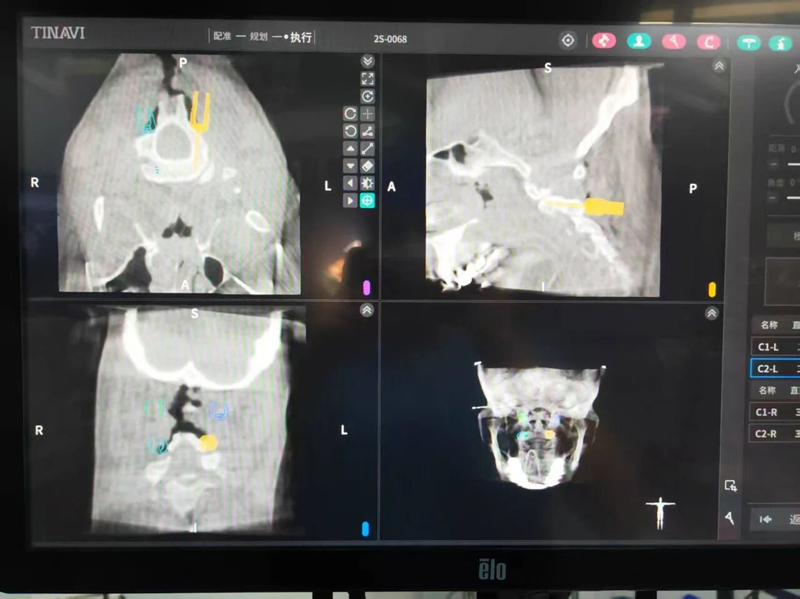

术中规划机器人操作

在患者病情平稳后,该手术由脊柱外科时愔主任团队张鹭博士主刀,手术团队在既往丰富手术经验之上,引入机器人技术,术中实现精准复位与智能化手术路径规划,为手术安全与术后效果提供了关键保障。凭借精湛技术和先进设备的完美结合,手术顺利完成,术后患者各项神经功能得到显著改善。